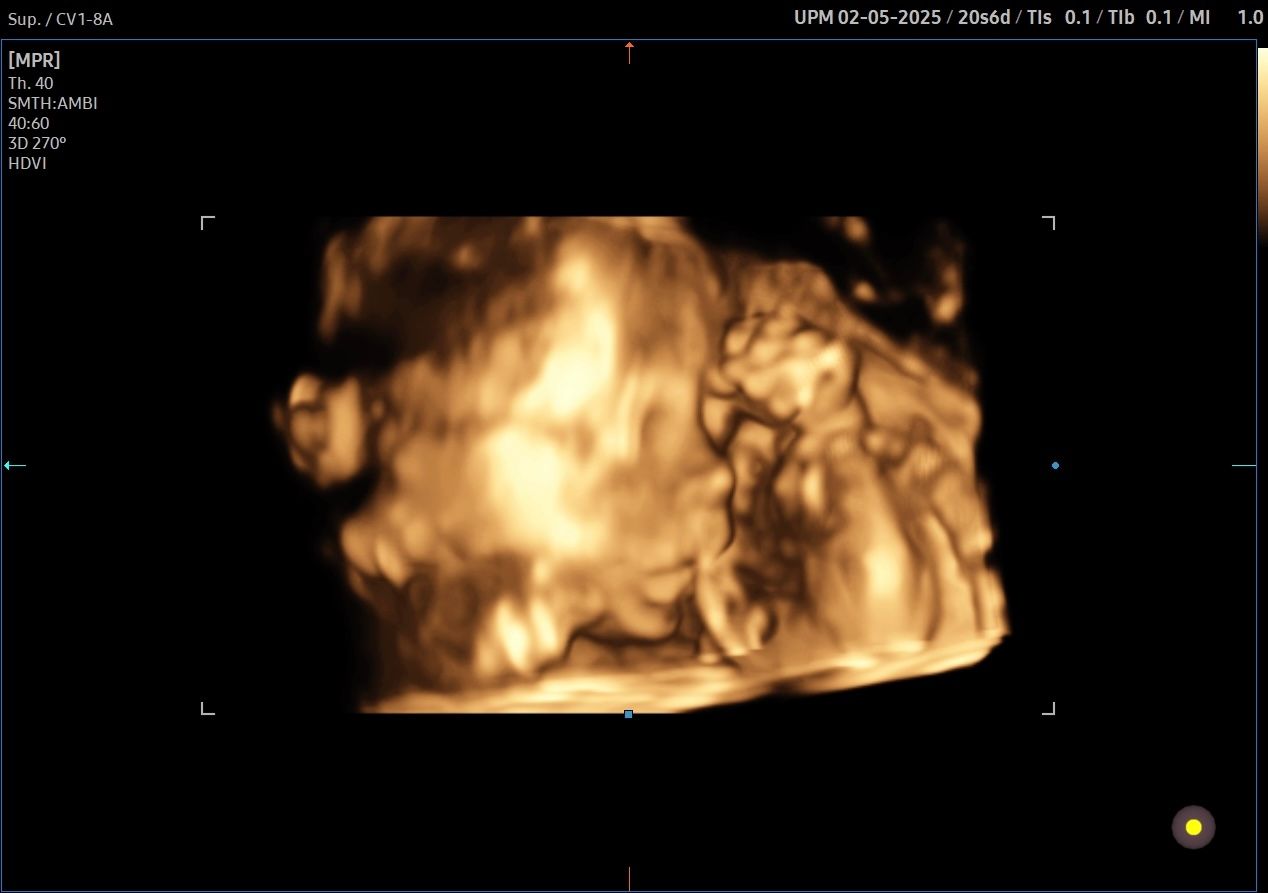

• Ecografia Ostetrica 3D/4D con Flussimetria materno-fetale

• M. G. Piccioni, F. Vena, Valentina Del Negro, V. D’Ambrosio, C. Capone, C. Donfrancesco, S. Tabacco, V. Tibaldi, S. Fruci, A. Giannini, M. C. Schiavi, L. Muzii, R. Brunelli, A. Giancotti. 3-D Ultrasound in the study of placental vascularization: application of vocal technique. A case-control study and a review of literature. Giorn. It. Ost. Gin. Vol XLI – n.2 Aprile-Giugno 2019